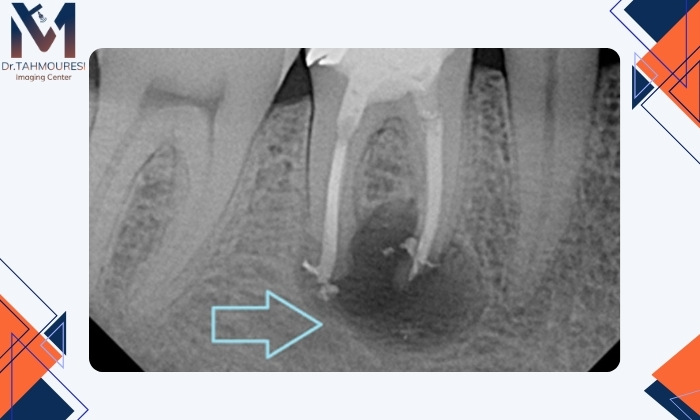

در تصاویر رادیولوژی دیجیتال دندان، عفونت معمولاً بهصورت ناحیهای تیره و با تراکم کمتر نسبت به سایر بخشها دیده میشود. این ناحیه نشاندهنده تحلیل استخوان اطراف ریشه و وجود باکتری یا التهاب است. متخصص رادیولوژی یا دندانپزشک از روی این الگوی خاص میتواند محل و شدت تقریبی عفونت را تشخیص دهد.